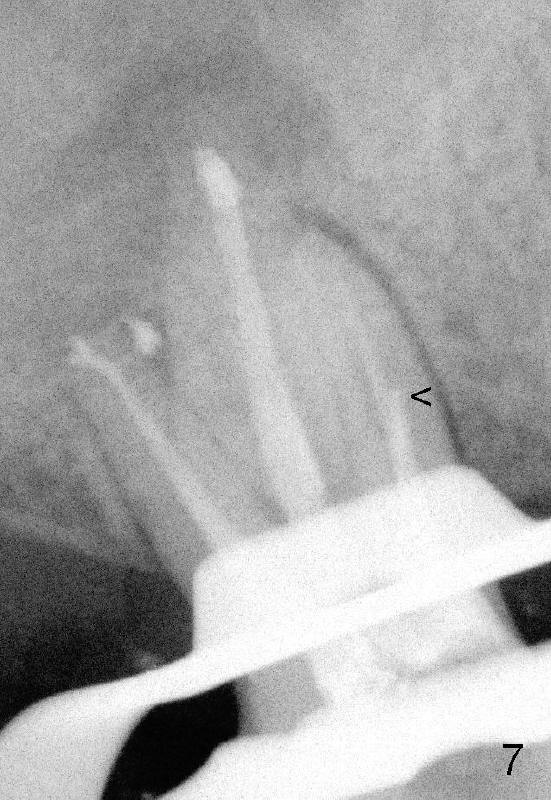

files达到不了工作长度(WL),但是衡量自己能力和时间,并没有进一步努力。时间还花在增加远中颊侧根和鄂侧根WL(其实没有必要,比较图四,图七),结果那里糊剂超充。副牙胶尖还充到原来ledge那里(图七箭头),如果第一次根管治疗就有CT指导,这样事情就有可能避免。图八显示根尖三分之一弯曲根管(黑线)与第一次根管扩大部分(红线)关系。